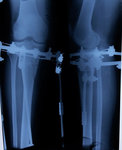

Рентген в 62 дня.

Сращение идёт отлично для этого срока и возраста пациентки.